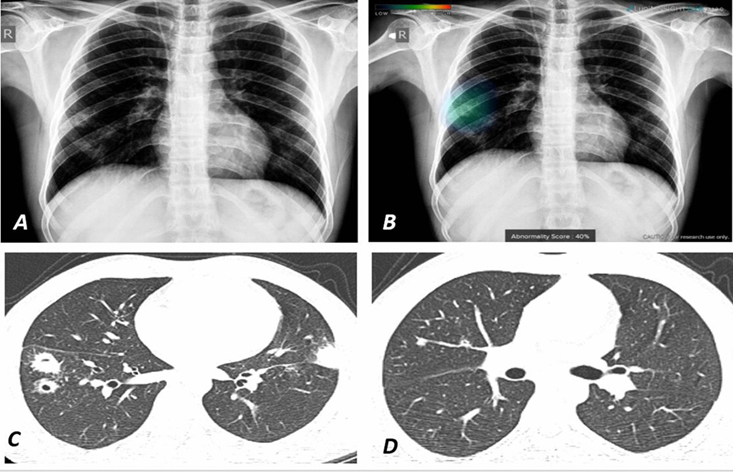

This chest radiograph demonstrates how AI-based software automatically detects pulmonary lesions and highlights the affected areas using a color overlay.

The color overlay visually represents both the location and severity of the lesions, helping clinicians identify abnormalities quickly and accurately.

Such AI-assisted diagnostic tools are particularly useful for detecting early-stage lung nodules and other subtle lesions that might otherwise be overlooked.